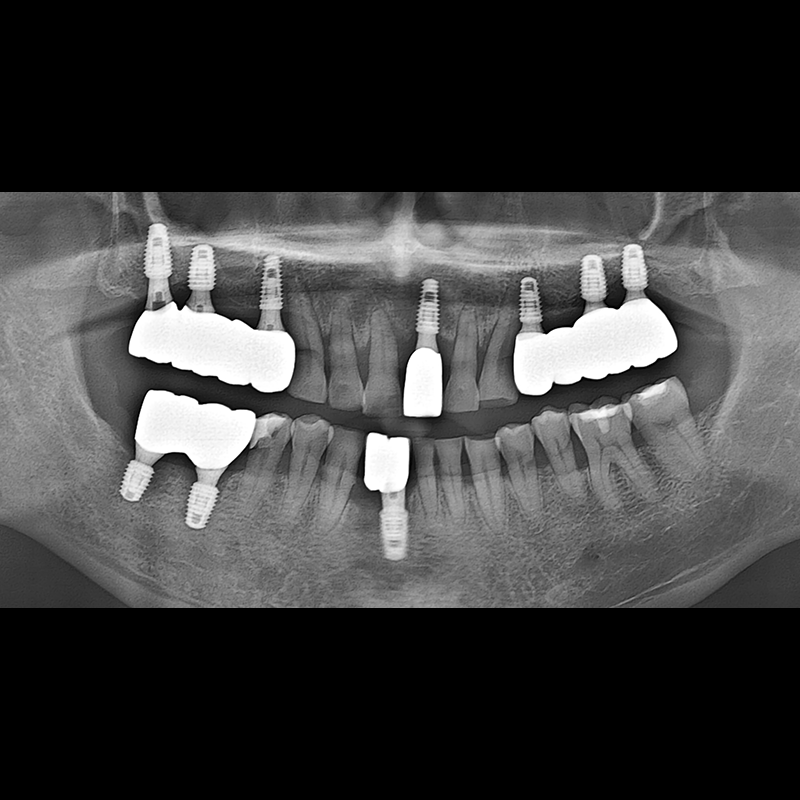

BEFORE AFTER

インプラント手術事例 2025.05.30

欠損した歯の部分と、生かしにくい歯の位置にインプラントを植立しました。